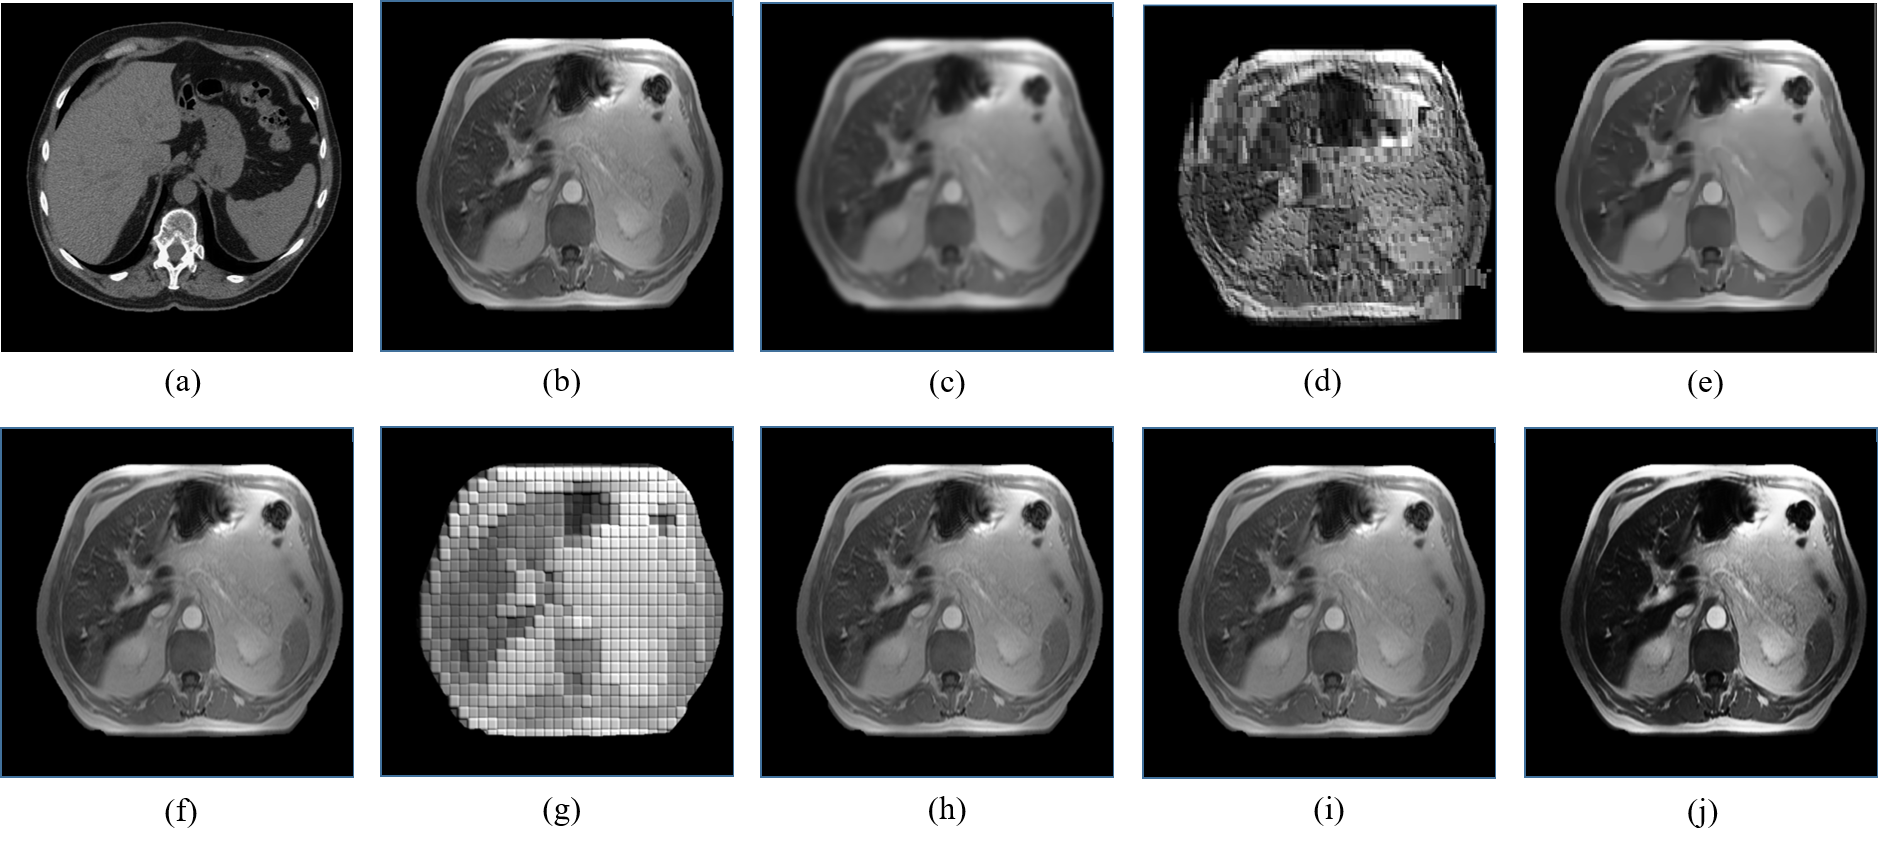

Figure 5: CT-MRI-CT unpaired image translation of a 41-year male abdomen using the proposed pCCGAN under different conditioning scenarios. (a) and (f) are real CT and MRI images, respectively, (b) Conditioning by images, (c) conditioning by average image, (d) conditioning by PDF, (e) CCGAN without augmentation, (g) conditioning by a patch of size 8×8888\times 8 pixels, (h) conditioning by patch of size 16×16161616\times 16 pixels, (i) conditioning by patch of size 32×32323232\times 32 pixels, and (j) conditioning by patch of size 64×64646464\times 64 pixels.

An additional CT to MRI abdomen image translation by all the conditioning scenarios is shown in Fig 5 (a) to (j). The real input abdomen CT image and corresponding target abdomen MRI image are shown in Fig. 5 (a) and Fig. 5 (f), respectively. Fig. 5 (b) presents the generated image from the proposed pCCGAN conditioned with images. One can observe that the edges are not clearly defined especially at the bottom part of the generated image. The output image generated by the conditioning of the average MRI image is displayed in Fig. 5 (c). Here, one can see that the image is a blur which leads to missing minute details. Fig. 5 (d) shows the result obtained by giving a PDF of an MRI image as the condition; one can make out from the image that the proposed CCGAN is not able to translate the input CT image to an MRI image. The output generated by the simple pCCGAN without augmentation is displayed in Fig. 5 (e). In this case, the image generated overshadows the low-frequency regions and the high-frequency region is enhanced. Fig. 5 (g) presents the image generated by the proposed pCCGAN when a patch of 8×8888\times 8 pixels is the condition provided. The network tries to translate the CT into MRI, however, the image remains patchy. The image generated by the conditioning of 16×16161616\times 16 pixels size patch is displayed in Fig. 5 (h). This conditioning helps the pCCGAN in optimal translation and restoration of the input CT image equivalent to the target MRI image as it utilizes the neighborhood pixel information also, both the high and low-frequency information is intact compared to the target modality. Fig. 5 (i) shows the result obtained by conditioning on patch size of 32×32323232\times 32 pixels. The low-frequency regions are not enhanced in this case, however, the image translation is comparable to the target image. The output obtained from conditioning on patch size of 64×64646464\times 64 is shown in Fig. 5 (j). In this case, the image contrast is increased and the high-frequency region is enhanced by a large amount. An ablation analysis with and without DiL is presented in Fig. 6 (a) to (c). The restored MRI with DiL shown in Fig. 6 (c) on the given MRI (Fig. 6 (a)) successfully reduces the noise content and artifacts present in the low and frequency portion of the images compared to the restored version without DiL (Fig. 6 (b)).